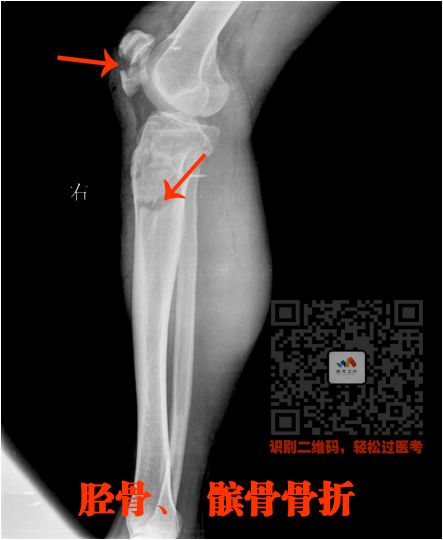

四、长骨骨折

就是四肢的长骨骨折

上肢:

肱骨、尺骨、桡骨

下肢:

股骨、股骨头、胫骨、腓骨

骨折非常简单的

这里就不讲解了,大家看片就行

看片